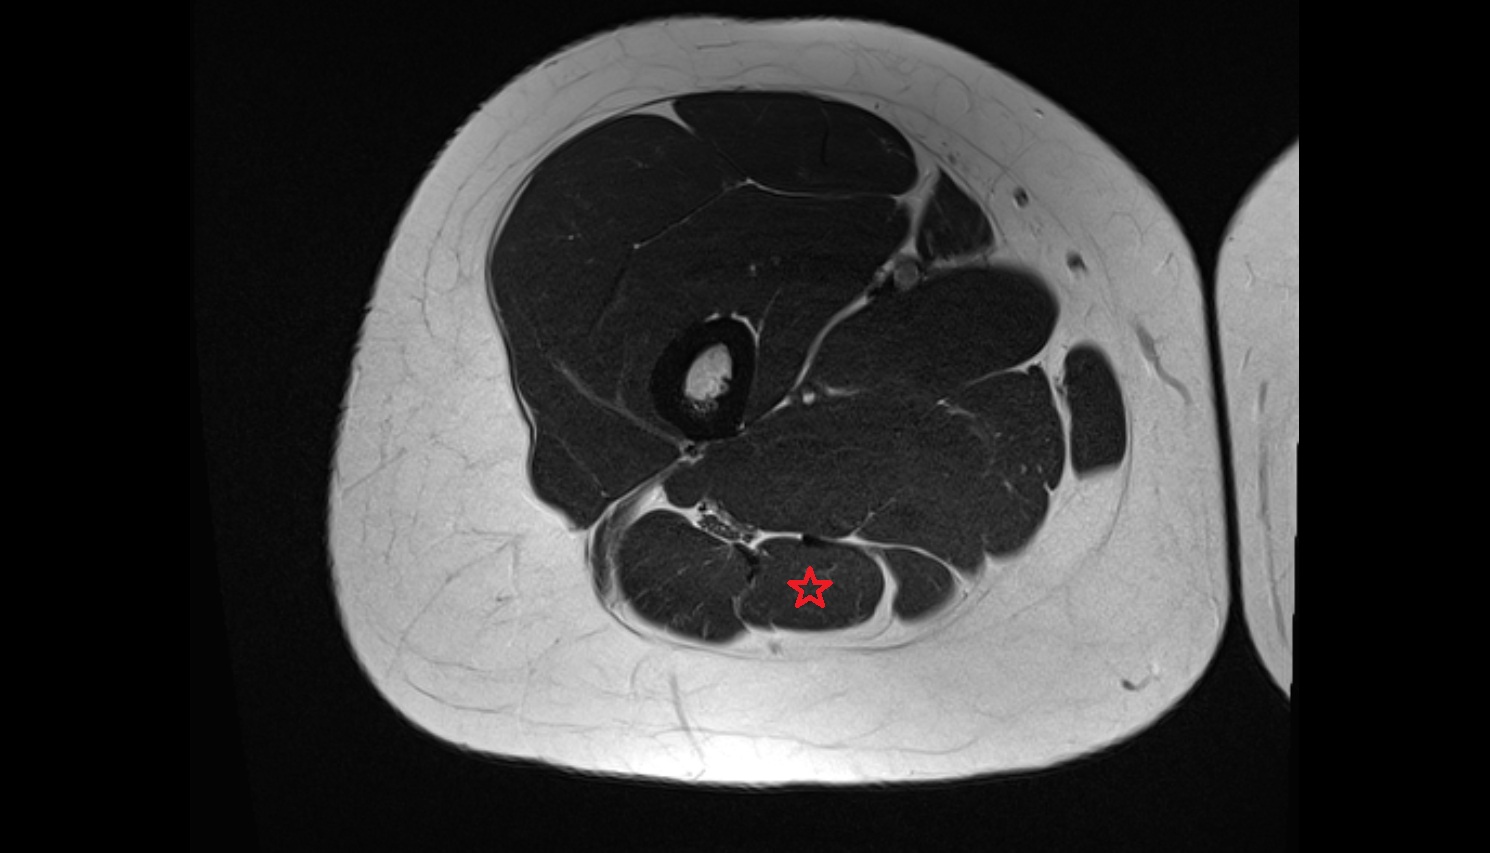

- Biceps femoris muscle (Short head)

- Biceps femoris muscle (Long head)

- Semitendinosus muscle

- Semimembranosus muscle

- Plantaris muscle

- Lateral head of gastrocnemius muscle

- Medial head of gastrocnemius muscle

- Gastrocnemius muscle

- Popliteus muscle

- Soleus muscle